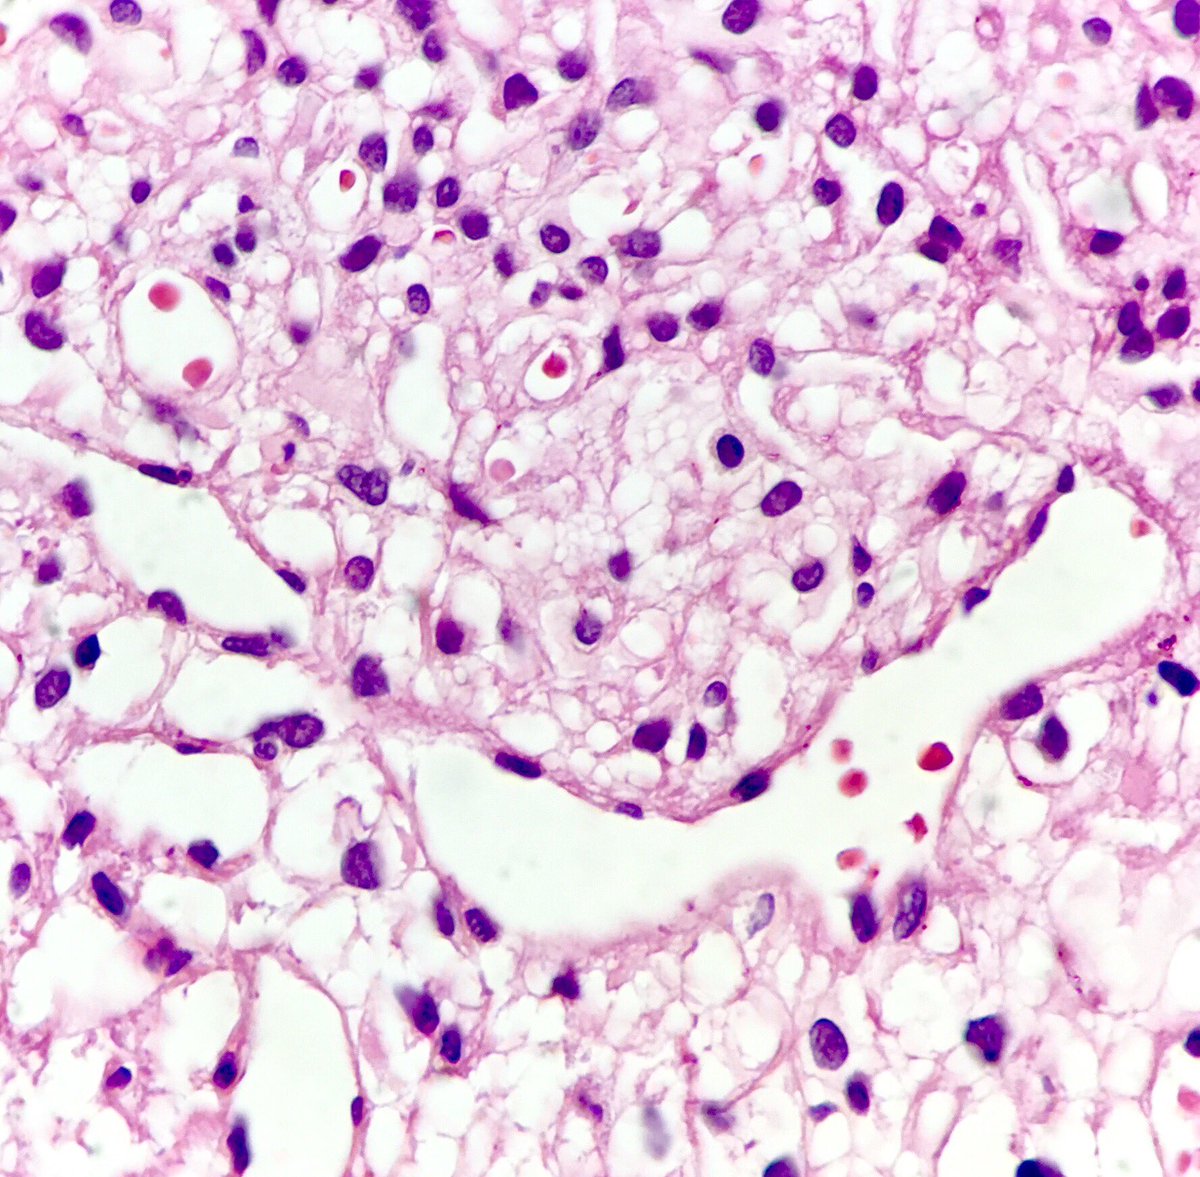

Two very different histologic patterns in the exact same pituitary adenoma.

#pathology#neuropath#pituitary#adenomapic.twitter.com/GKO6yLBrw7